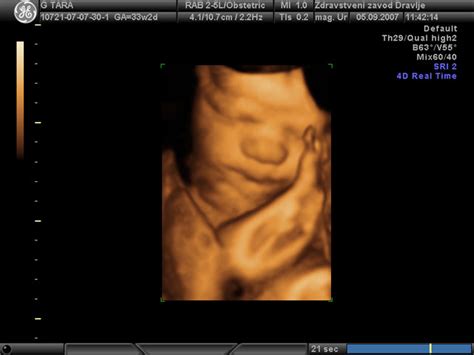

Prezgodnji porod je intenzivno krčenje materničnih mišic, ki ga občutimo precej pred 37. tednom nosečnosti. Včasih pride do prezgodnjega poroda, ko zaradi krčenja maternice pride do odprtja materničnega vratu po 20. tednu in pred 37. tednom nosečnosti. Med zgodnjim porodom lahko rodite nedonošenčka. Normalno obdobje nosečnosti je običajno 40 tednov.

V primeru prezgodnjega poroda, ko je otrok nedonošenček, je čas bivanja v bolnišnici pogosto daljši. Nedonošenčki potrebujejo dodatno nego in nadzor, pogosto v inkubatorjih, dokler ne dosežejo stabilnega stanja. Če pride do zapletov pri porodu ali po njem, se lahko čas bivanja v bolnišnici podaljša.

V primeru prezgodnjega poroda, ko je otrok nedonošenček, je pomembno, da se zavedate, da bo morda potreboval dodatno nego in čas v bolnišnici. Vendar pa sodobna medicina omogoča izboljšanje preživetja in zmanjšanje obolevnosti tudi pri najmlajših nedonošenčkih.